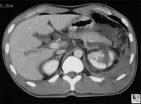

Renal injuries can be classified into four large categories based on imaging findings. Category I renal injuries include minor cortical contusion, subcapsular hematoma, minor laceration with limited perinephric hematoma, and small cortical infarct. Category II lesions include major renal lacerations extending to the medulla with or without involvement of the collecting system and segmental renal infarct. Category III lesions are catastrophic renal injuries and include multiple renal lacerations and vascular injury involving the renal pedicle. Category IV injuries are ureteropelvic junction injuries.

CT is particularly useful in evaluating traumatic injuries to kidneys with preexisting abnormalities and can help assess the extent of penetrating injuries in selected patients with limited posterior stab wounds. Integration of the imaging findings in renal injury with clinical information is critical in developing a treatment plan.